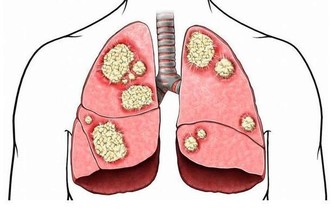

3、經常咳嗽,或者出現痰中帶血:肺癌是我國發病率和死亡率最高的癌症。肺癌患者中通常為長期抽煙的人,肺部腫瘤初期一般都是表現為各種慢性肺炎,其表現就是咳嗽(大家一定要和哮喘、支氣管炎區分開來)。 4、通常大家將胸腔以下的腹部稱為肚子,這個範圍較大。肚子疼與很多原因有關,但如果表現為臍周和下腹部疼痛,則往往是腸道病變。 5、胸部出現灼熱感或者莫名的胸痛、胸悶、氣短:胸部出現灼熱感是食道損傷的一個常見症狀,如果大家最近兩三個月頻繁出現灼熱感或者莫名的胸部疼痛,那就要要警惕食道癌或者胃癌了。